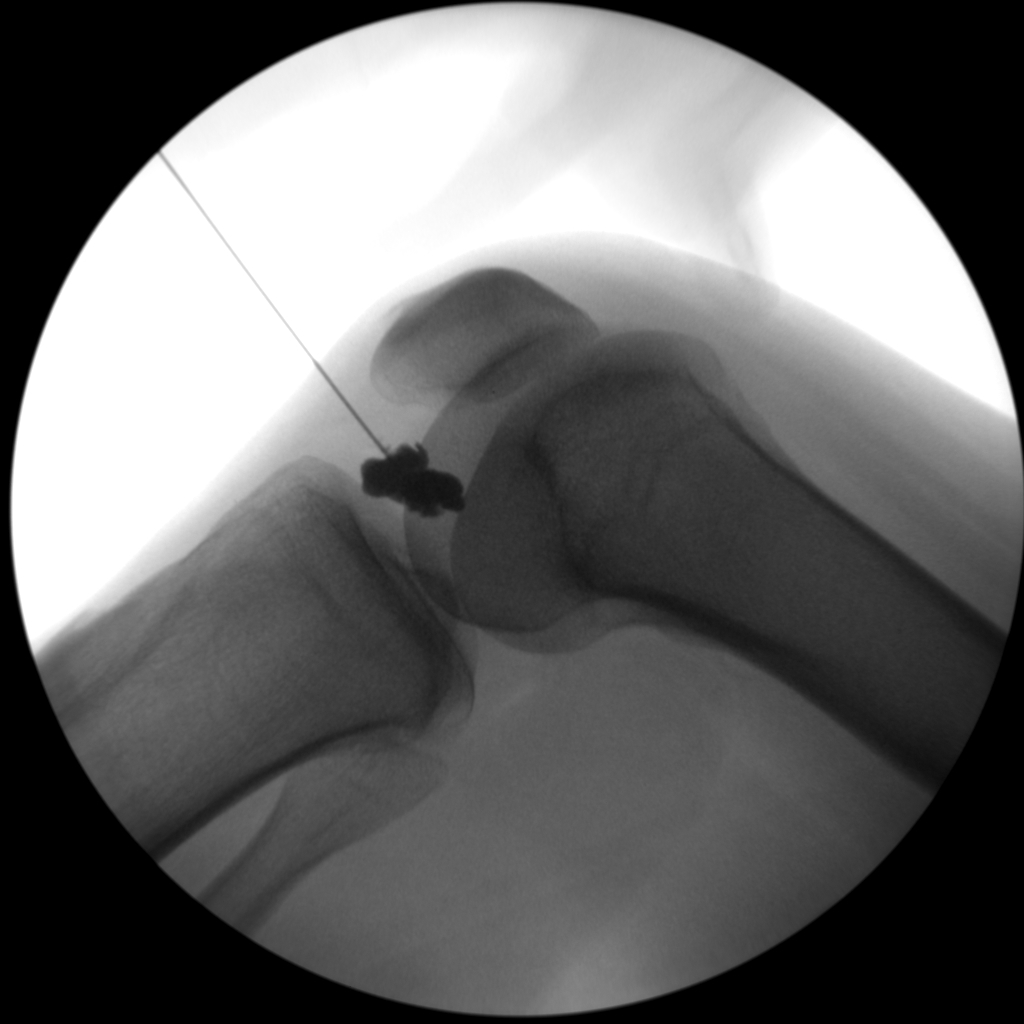

Joint Injections

Skan-C proves highly effective in performing joint injections, a procedure commonly used to administer pain-relieving medication directly into the affected joints, such as the knee, shoulder, or hip.